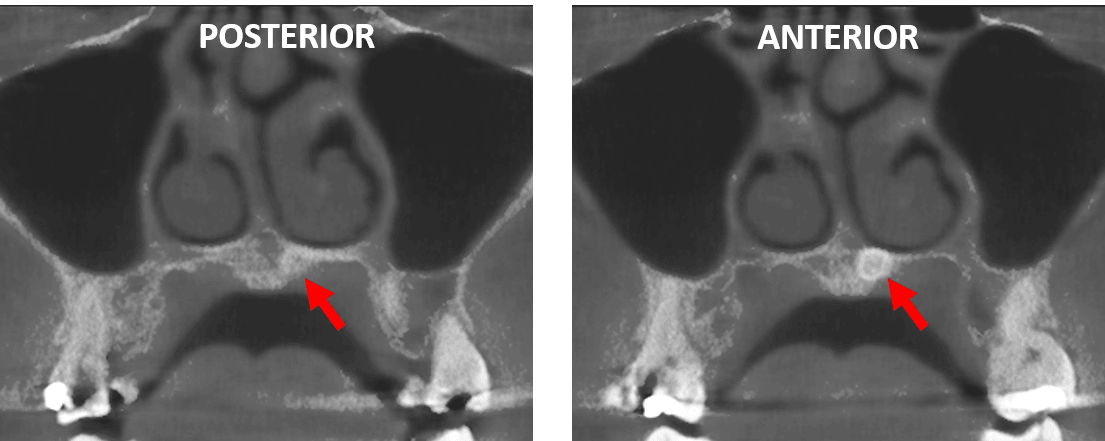

Fig.3

En cortes axiales (Fig.3), se observa que se trata de un diente supernumerario, evidenciando una forma cónica orientado hacia el lado izquierdo de paladar.